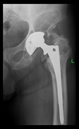

The radiological examination allowed us to verify the close bone-to-implant contact and the unchanged position of the implant during follow-up.

In all the cases operated with the above-described targeting procedure, the stems of the cups remained between the cortical bone surfaces without perforation of the linea terminalis, as shown by postoperative radiographs. There were no complicated surgical situations. In 16 cases, the wound healings were uneventful, and the hips were able to bear weight again after postoperative rehabilitation.